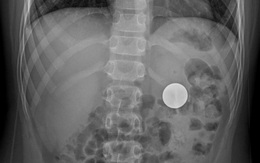

Gắp đồng xu trong dạ dày bệnh nhi 11 tuổi

Bệnh viện Hoàn Mỹ Sài Gòn đã tiếp nhận và xử lý thành công một trường hợp bệnh nhi 11 tuổi nuốt phải đồng xu có đường kính 4cm.